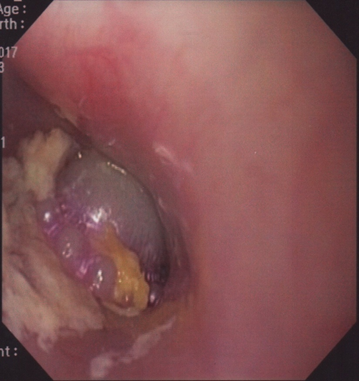

Age distribution of patients shown in Table 1, Foreign body was commonly seen 22 (75.9%) in 1-5 years of age, as shown in Table 1. Table 2 shows sex distribution of foreign body ingestion cases, where 15 (51.7%) were male child. Among the ingested foreign bodies only 3 (10.3%) were removed within 24 hours of ingestion, 10 (34.5%) cases were removed between 24-48 hours and the remaining 16 (55.2%) were removed after 48 hours (Table 3). Coin was the most commonly ingested foreign body 19 (65.5%). Other foreign bodies were metallic chain 3 (10.3%), button battery 2 (6.9%), others 5 (17.2%), (Figure 1 - Figure 3). Most of the ingested foreign bodies were found in the stomach, few were in upper esophagus (Table 4). There were no complications either during endoscopy or after foreign body removal.

Figure 1 Various ingested foreign bodies removed by using Olympus CV-150 model endoscopy.

Figure 2 Endoscopic picture showing an ingested foreign body of 3-year-old child.